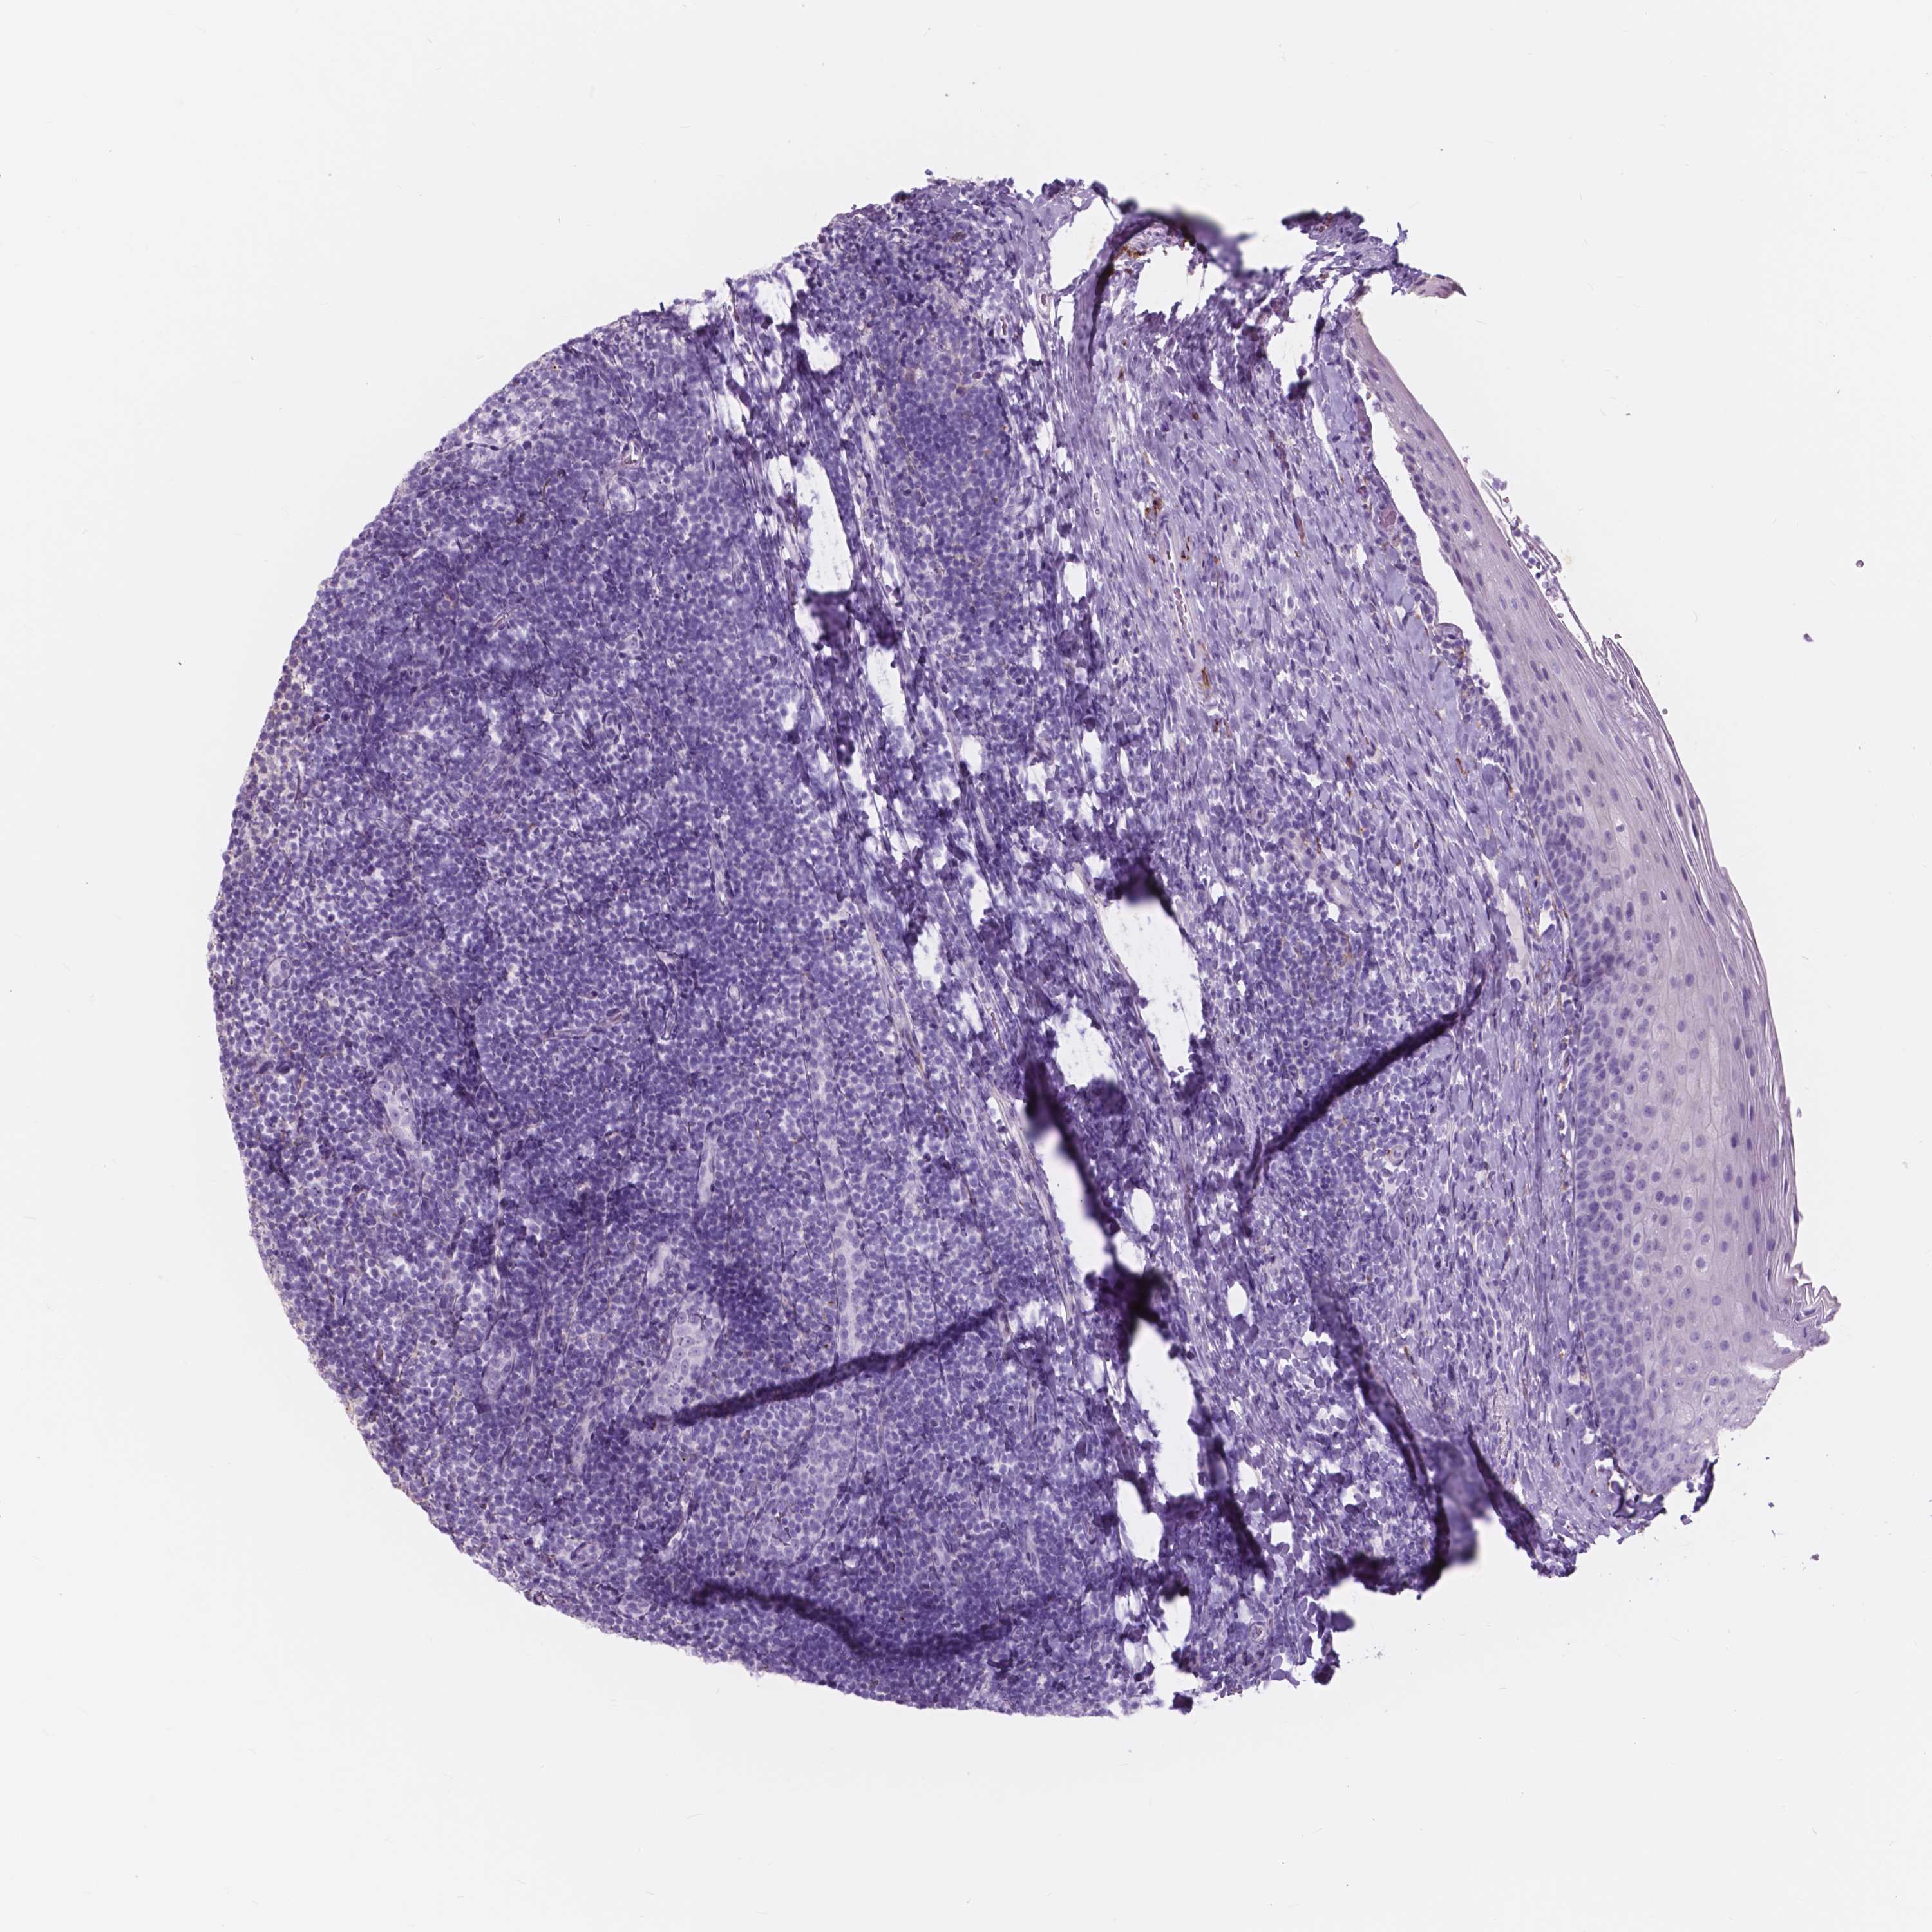

FXYD2